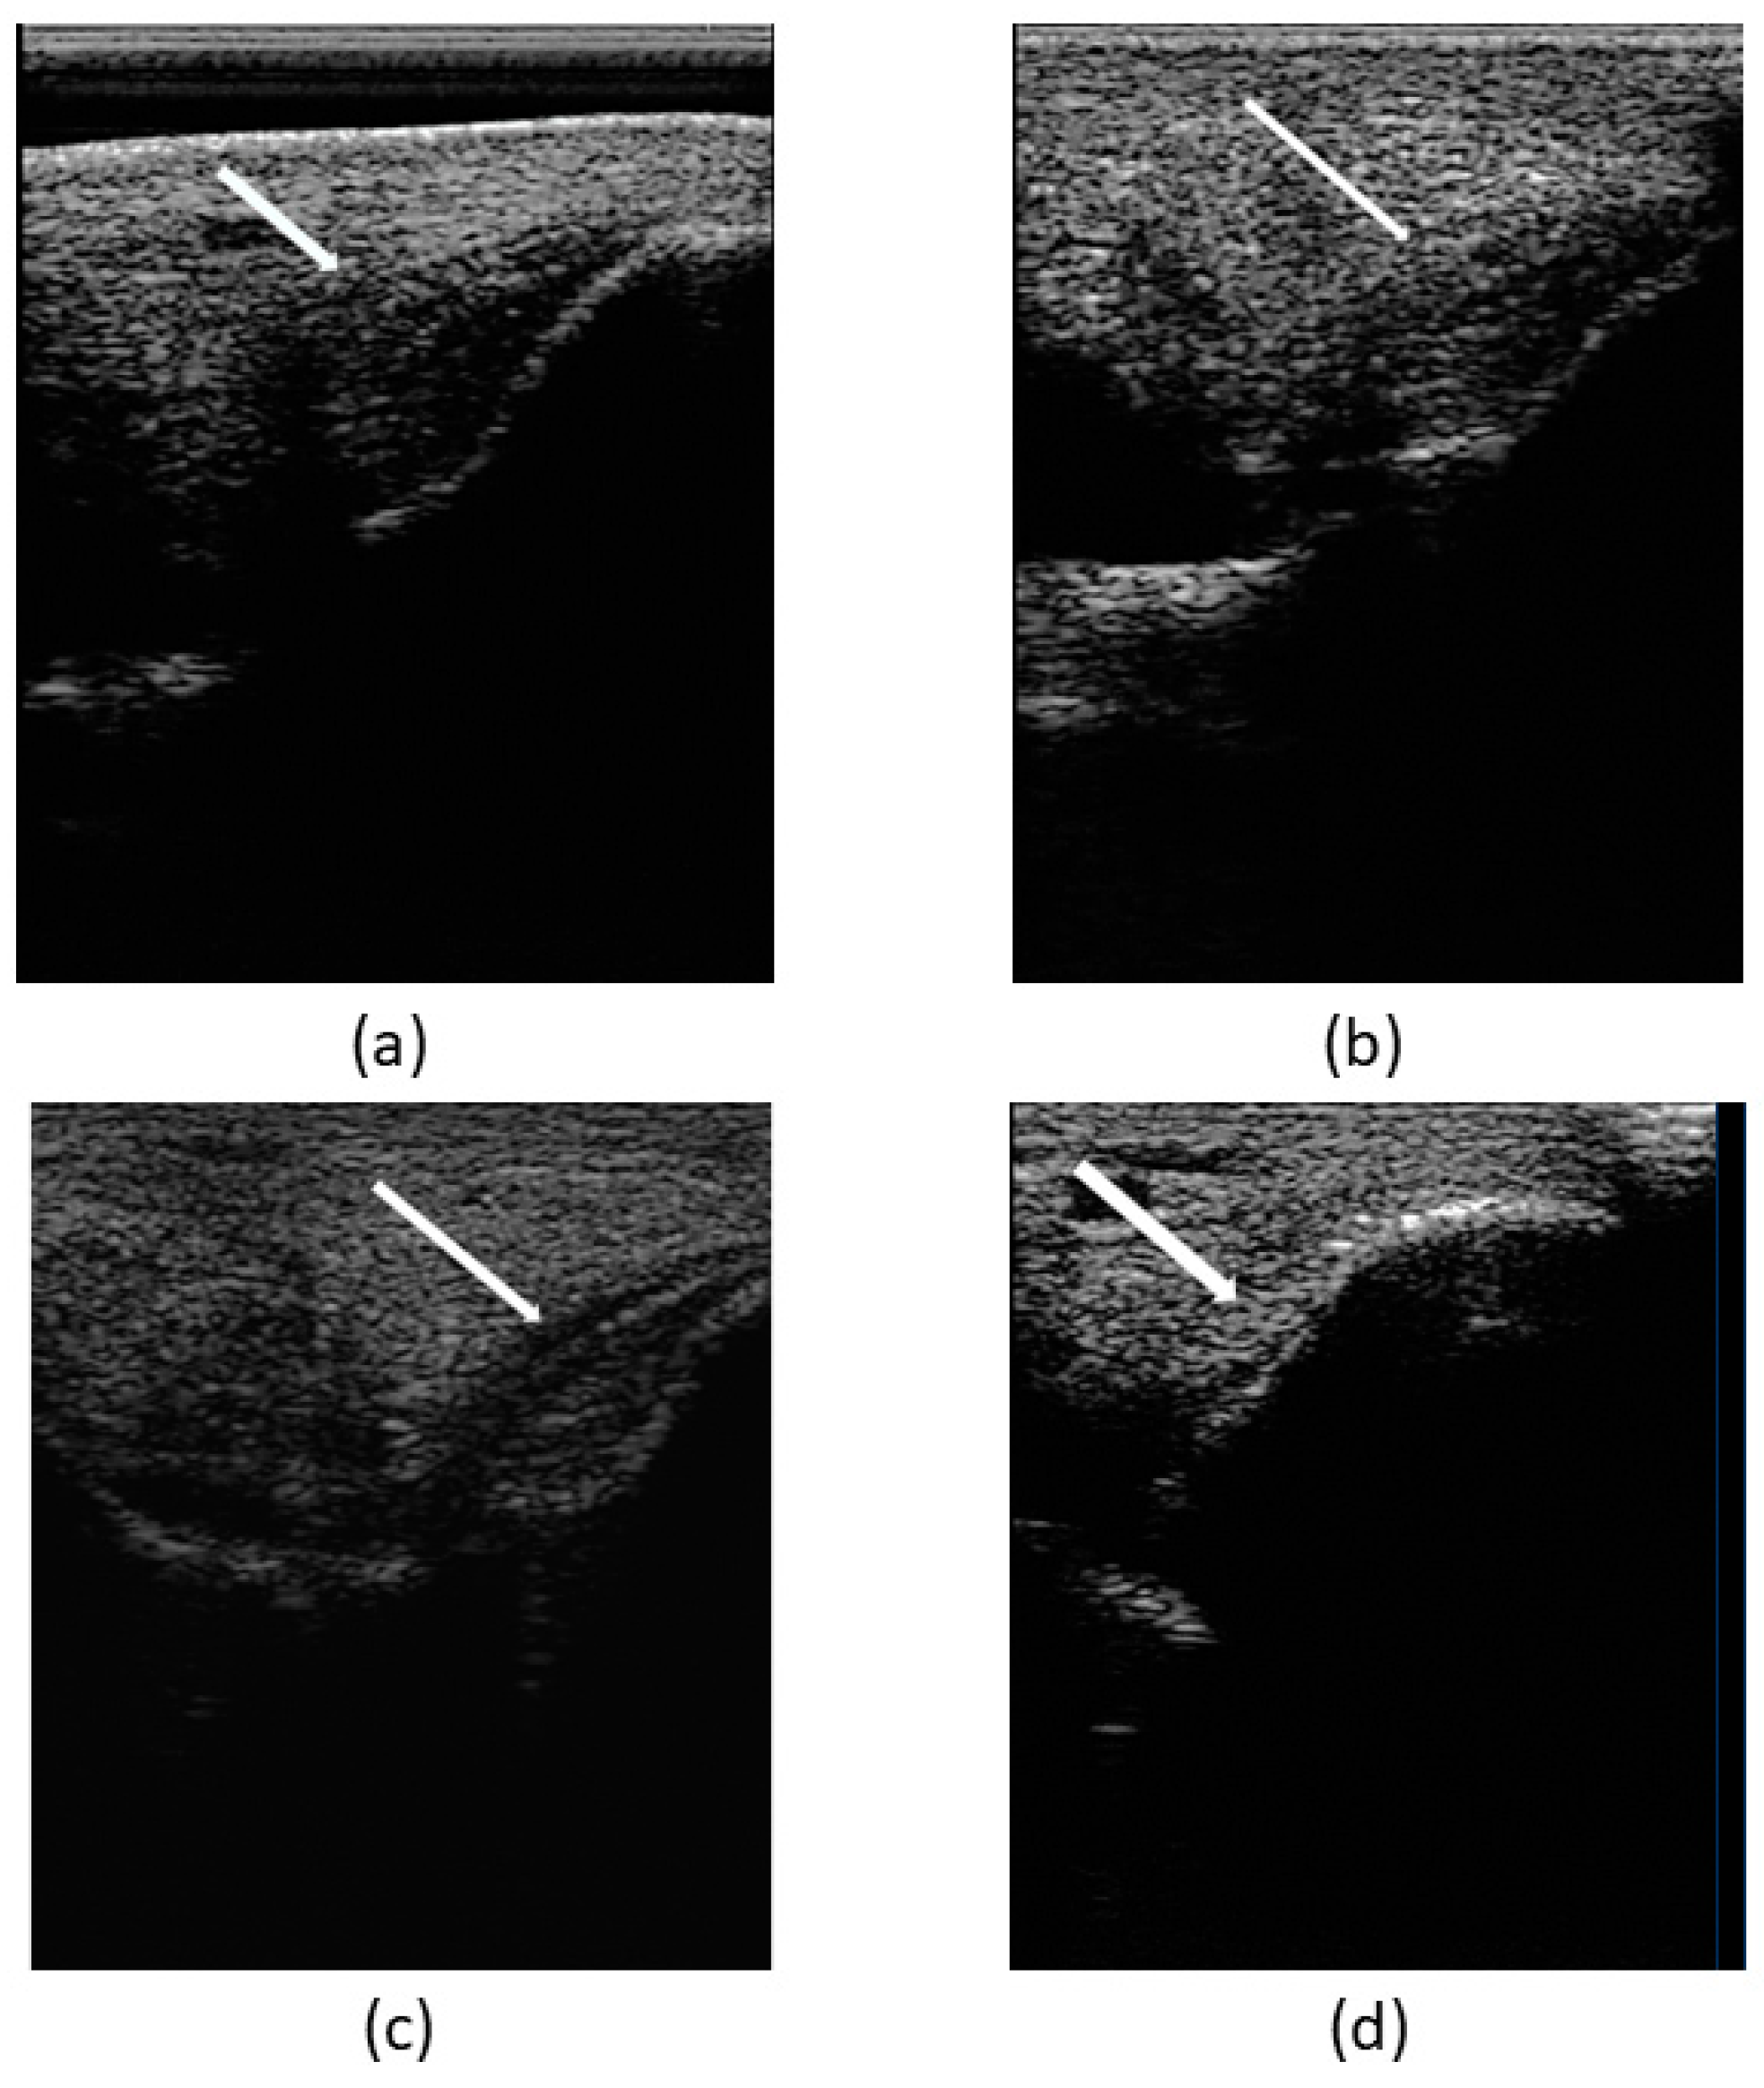

To sum up, the assessment of the patient’s clinical recovery was performed by the presence of no pain in the tarsus and no lameness achieved by day 30. Lesion ultrasonographic improvement and indicators of regeneration were evidenced by a progressive increase in echogenicity and fiber alignment, and decrease in ligament cross-sectional area and synovial fluid accumulation within the joint space, observed through ultrasound examination during the follow-up on days 1 (T0), 15 (T1), 30 (T2), 45 (T3), and 60 (T4) (Figure 8).

Figure 8.

Images of ultrasonographic follow-up. (a) Day 1 (T0), (b) day 15 (T1), (c) day 30 (T2), and (d) day 60 (T3). Indicators of ligamentous regeneration: increased echogenicity and fiber alignment, as well as decrease in cross-sectional area and synovial fluid accumulation within the joint space.

On day 30 (T2), there was no evidence of pain and lameness (grade 0/5). Ultrasonographic evaluation evidenced increased echogenicity of the lesion as well as a reduction in the cross-sectional area with good fiber alignment. The tarsocrural joint swelling and oedema were reduced. Nevertheless, compared with the contralateral limb, the right tarsocrural joint diameter was still larger than the left.

Over the course of the follow-up ultrasonographic examinations, an increasing echogenicity of the lesion was evidenced, as well as a reduction in the cross-sectional area, good fiber alignment, and a reduction of the abnormal synovial fluid. On day 60 (T4), two months after the first treatment, there was a complete recuperation of the ligament structure—lesion completely fulfilled, good echogenicity, good fiber alignment, and normal cross-sectional area—compatible with adequate tissue regeneration. No pain and no lameness were present, and there were also no signs of cartilage remodeling. Despite this achievement, a physical rehabilitation program proceeded until day 90 (T5).